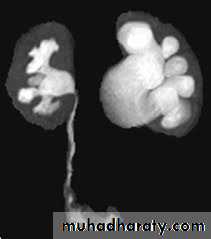

IVUDIAGNOSIS